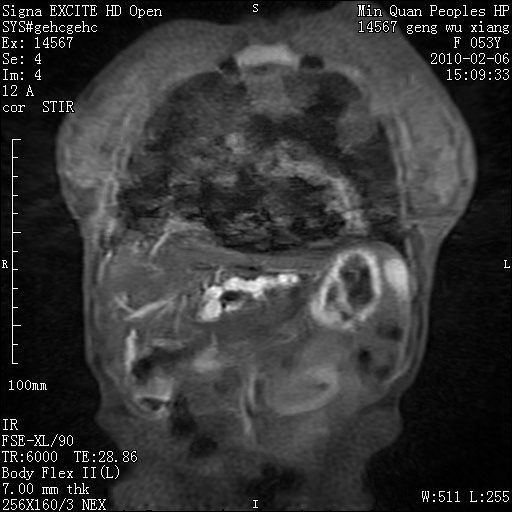

标题: MRI2762:胆道梗阻原因?

f,53y,全身黄染多日。

高位胆道梗阻 胆管癌可能性大

支持 高位胆道梗阻 胆管癌可能性大。